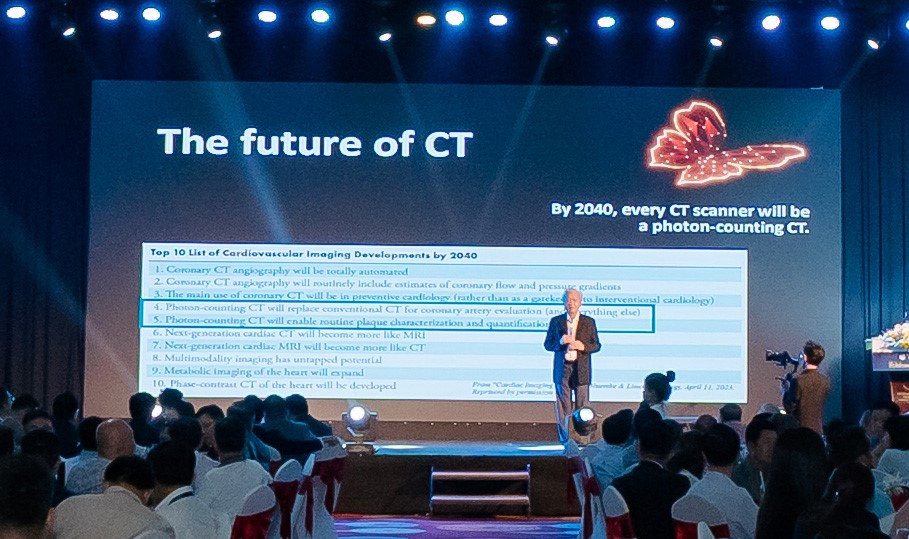

Tương lai của chẩn đoán hình ảnh đang dần thay đổi

Hiện nay, công nghệ cắt lớp vi tính lượng tử đã được triển khai tại hơn 35 quốc gia, với hơn 2,5 triệu bệnh nhân và hơn 1.000 nghiên cứu khoa học được công bố. Tại Việt Nam, công nghệ này cũng đang dần được tiếp cận trong các bệnh viện và hội nghị chuyên ngành.

PGS.TS.BS. Võ Tấn Đức chia sẻ về công nghệ cắt lớp vi tính lượng tử tại Hội nghị khoa học Chẩn đoán hình ảnh TPHCM mở rộng lần thứ XIII năm 2026

“Trong tương lai không xa, công nghệ cắt lớp vi tính lượng tử có thể trở thành tiêu chuẩn mới trong chẩn đoán hình ảnh”, PGS.TS.BS. Võ Tấn Đức – Chủ tịch Hội Chẩn đoán hình ảnh TPHCM nhận định.

Khi đó, giá trị của một hệ thống CT sẽ không chỉ nằm ở việc tạo ra hình ảnh rõ nét, mà ở khả năng hỗ trợ bác sĩ đưa ra quyết định chính xác và giúp người bệnh có cơ hội được phát hiện sớm, điều trị kịp thời ngay từ những giai đoạn đầu.